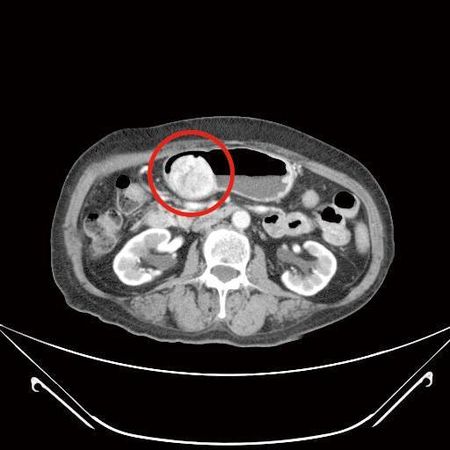

▲患者胃腸道基質瘤已經有6公分大小。(圖/國泰醫院提供)

72歲林女士,3年前經上消化道內視鏡檢查發現有個2公分大的胃黏膜下腫瘤,疑似胃腸道基質瘤,持續門診追蹤,近期發現腫瘤緩慢長大,2個月前因上腹部悶痛且頭暈就診,由於合併有血便症狀,經上消化道內視鏡及電腦斷層檢查,發現腫瘤已接近6公分大,同時膽囊被結石塞滿,已經沒有膽汁的空間,最後透過微創手術進行部分胃切除以及膽囊切除,一次完成治療。

蔡欣恬指出,胃腸道基質瘤手術的目標在於完整將腫瘤切除,以往這類患者需接受超過15公分傷口的剖腹手術(傷口位於腹部正中間),考量病人合併有膽結石問題,所以建議接受達文西系統機器手臂輔助腹腔鏡手術,不但可以做更細緻的剝離及切除,也可同時處理胃部惡性腫瘤及膽結石。